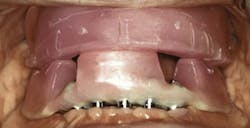

What is the need to support facial esthetics and lip support? If patients have lost a significant amount of bone, restorations may require denture flanges to provide support for the lips and facial esthetics, thus eliminating a hybrid as a treatment option (figure 1).

Figure 1: Lack of lip support